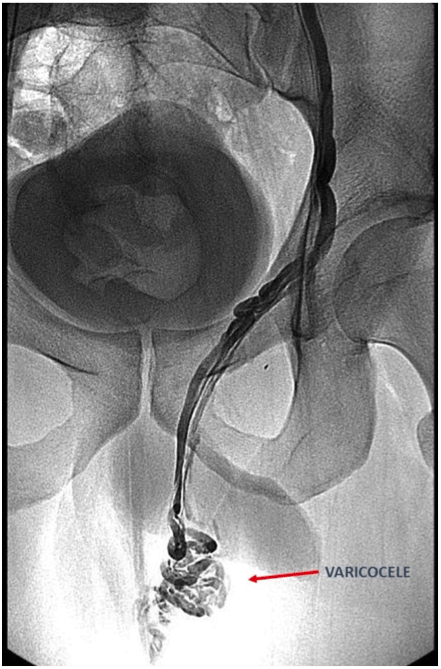

Il più frequente è l'aneurisma dell'aorta addominale quando questa si allarga a oltre 3 cm. Varicocele | Sociedad Española de Radiología Vascular e

Varicocele | Sociedad Española de Radiología Vascular e from servei.org